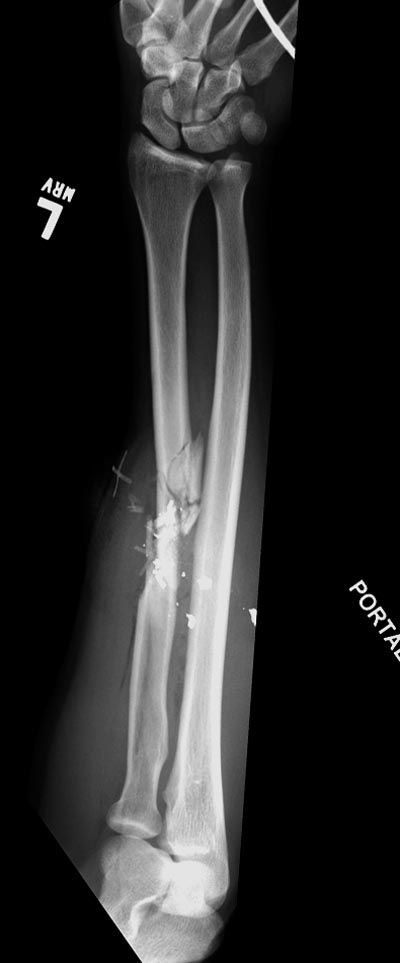

Здесь примеры: двоюродные братья с ранением предплечья, у одного локтевая, а у второго лучевая. В следующее утро локтевая фиксирована без обнажения фокуса травмы из небольших доступов, а второй из обычного волярного доступа. А клинический снимок из прошлых операций...